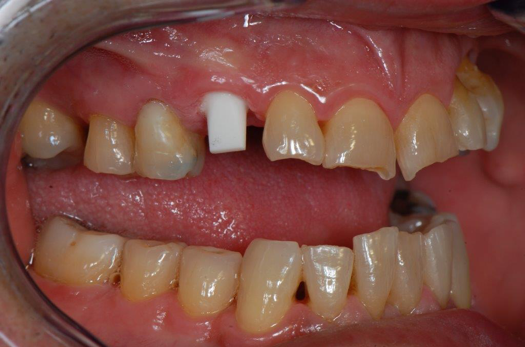

Fig 18. Preoperative image.

Figure 18

Occasionally dentists are presented with extreme challenges with long-term restorations and replacing missing teeth. Dentists must evaluate the patient's condition, develop optimum long-term oral health, and attempt to meet the patient's expectations. Figure 18 showed a class III malocclusion with deep bite, multiple abfractions, and less-than-ideal occlusal plane, but the patient wanted to replace his maxillary right canine only. A discussion with the patient regarding occlusal disharmonies and comprehensive recommendations for full-mouth rehabilitation revealed that the patient had a limited budget for dental care. The patient understood the ramifications of his comprehensive dental needs not being affordable. Decisions were made to atraumatically remove the maxillary right canine (Figure 19) and immediately place a ceramic dental implant (Figure 20). Polytetrafluoroethylene (PTFE) 4-0 sutures were placed to help support soft tissues, and then a full-arch Essix-style retainer with a flowable composite facial veneer was used to provide some esthetics during the patient's healing phase (Figure 21). The implant and the retainer were not to be in contactthe retainer may occlude with the opposing dentition and also be passive in relation to the ceramic implant.